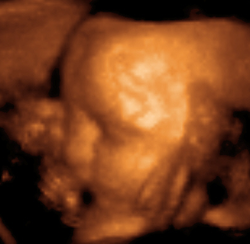

تتضمن تلك الاستعمالات التي تستخدم فيها الموجات فوق الصوتية في الحصول على المعلومات فقط. على سبيل المثال، يستخدم الأطباء الموجات فوق الصوتية للتأكد من نمو الأجنة0 ويمكن لبعض معدات الموجات فوق الصوتية رسم صورة الجنين على شاشة. كما تساعد هذه المعدات أيضاً في تشخيص الأورام وحصوات المرارة وأمراض القلب، علاوة على بعض الاضطرابات الأخرى. ويعتقد معظم الأطباء أنه لاتوجد آثار جانبية خطيرة للفحوص التي تستخدم فيها الموجات فوق الصوتية.